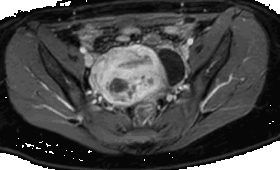

सब्म्यूकस सिस्टिक एडेनोमायोसिस का हाइस्टेरोस्कोपिक प्रबंधन, इस स्थिति का निदान और उपचार करने के लिए एक कम से कम आक्रामक दृष्टिकोण शामिल करता है। सब्म्यूकस सिस्टिक एडेनोमायोसिस गर्भाशय के अंत:धरणी लिंग में सिस्टों की मौजूदगी को संकेत करता है। हाइस्टेरोस्कोपी योनिकांग में डालकर इन सिस्टों को सीधे देखने और निकालने की सुविधा प्रदान करती है, जिससे लक्षणों में राहत और बांझपन की संभावनाएं सुधारती हैं। यह प्रक्रिया मुक्तियां या विनाश करते हुए विशेषज्ञ उपकरणों का उपयोग करके की जाती है। हाइस्टेरोस्कोपिक प्रबंधन के लाभों में कम समय में सुखाने, ऑपरेशन के बाद के संभावित जटिलताओं की कमी और गर्भाशय की संरक्षण की सुविधा शामिल हैं, जिससे यह सब्म्यूकस सिस्टिक एडेनोमायोसिस का उपचार करने के लिए एक प्रभावी और सुरक्षित विकल्प है।